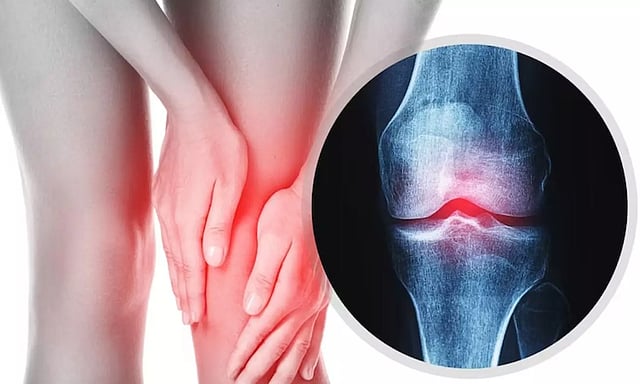

மூட்டுகளில் ஏற்படுகின்ற காயங்கள் அல்லது புண்கள், இவற்றால் வீக்கம் அல்லது வலி ஏற்படுகிறது. மூட்டுகளில் உள்ள குருத்தெலும்புகள், தசைநார்கள், எலும்புகள் அல்லது தசைகளுக்குள் ஏற்படும் காயங்களாலும் மூட்டுவலி வருகிறது. ஆனால் பெரும்பாலும் குருத்தெலும்பு தேய்வால் வருகின்ற கீல்வாதம் தான் அதிகம். எலும்பில் உள்ள குருத்தெலும்பு தேய்வால் வருகின்றது.

இவ்வகை மூட்டுவலி வயதானவர்களையும், பெண்களையும் மிக அதிகமாக பாதிக்கிறது. இந்த வகை வாதத்தில், கால் மூட்டுகளில் உள்ள எலும்புகளின் முனைகளை, குஷன் போன்று பாதுகாக்கும் குருத்தெலும்பு படிப்படியாக பலவீனமடைந்து, இறுதியாக, குருத்தெலும்பு முற்றிலும் தேய்ந்துவிடுகிறது. மூட்டுகளிடையே உள்ள சினோவியல் திரவமும் அளவில் குறைகிறது. இதனால் கால் முட்டி எலும்புகள் ஒன்றுடன் ஒன்று உரசி, கடுமையான கால் வலி, வீக்கம், சூடு இவற்றை ஏற்படுத்துகிறது.